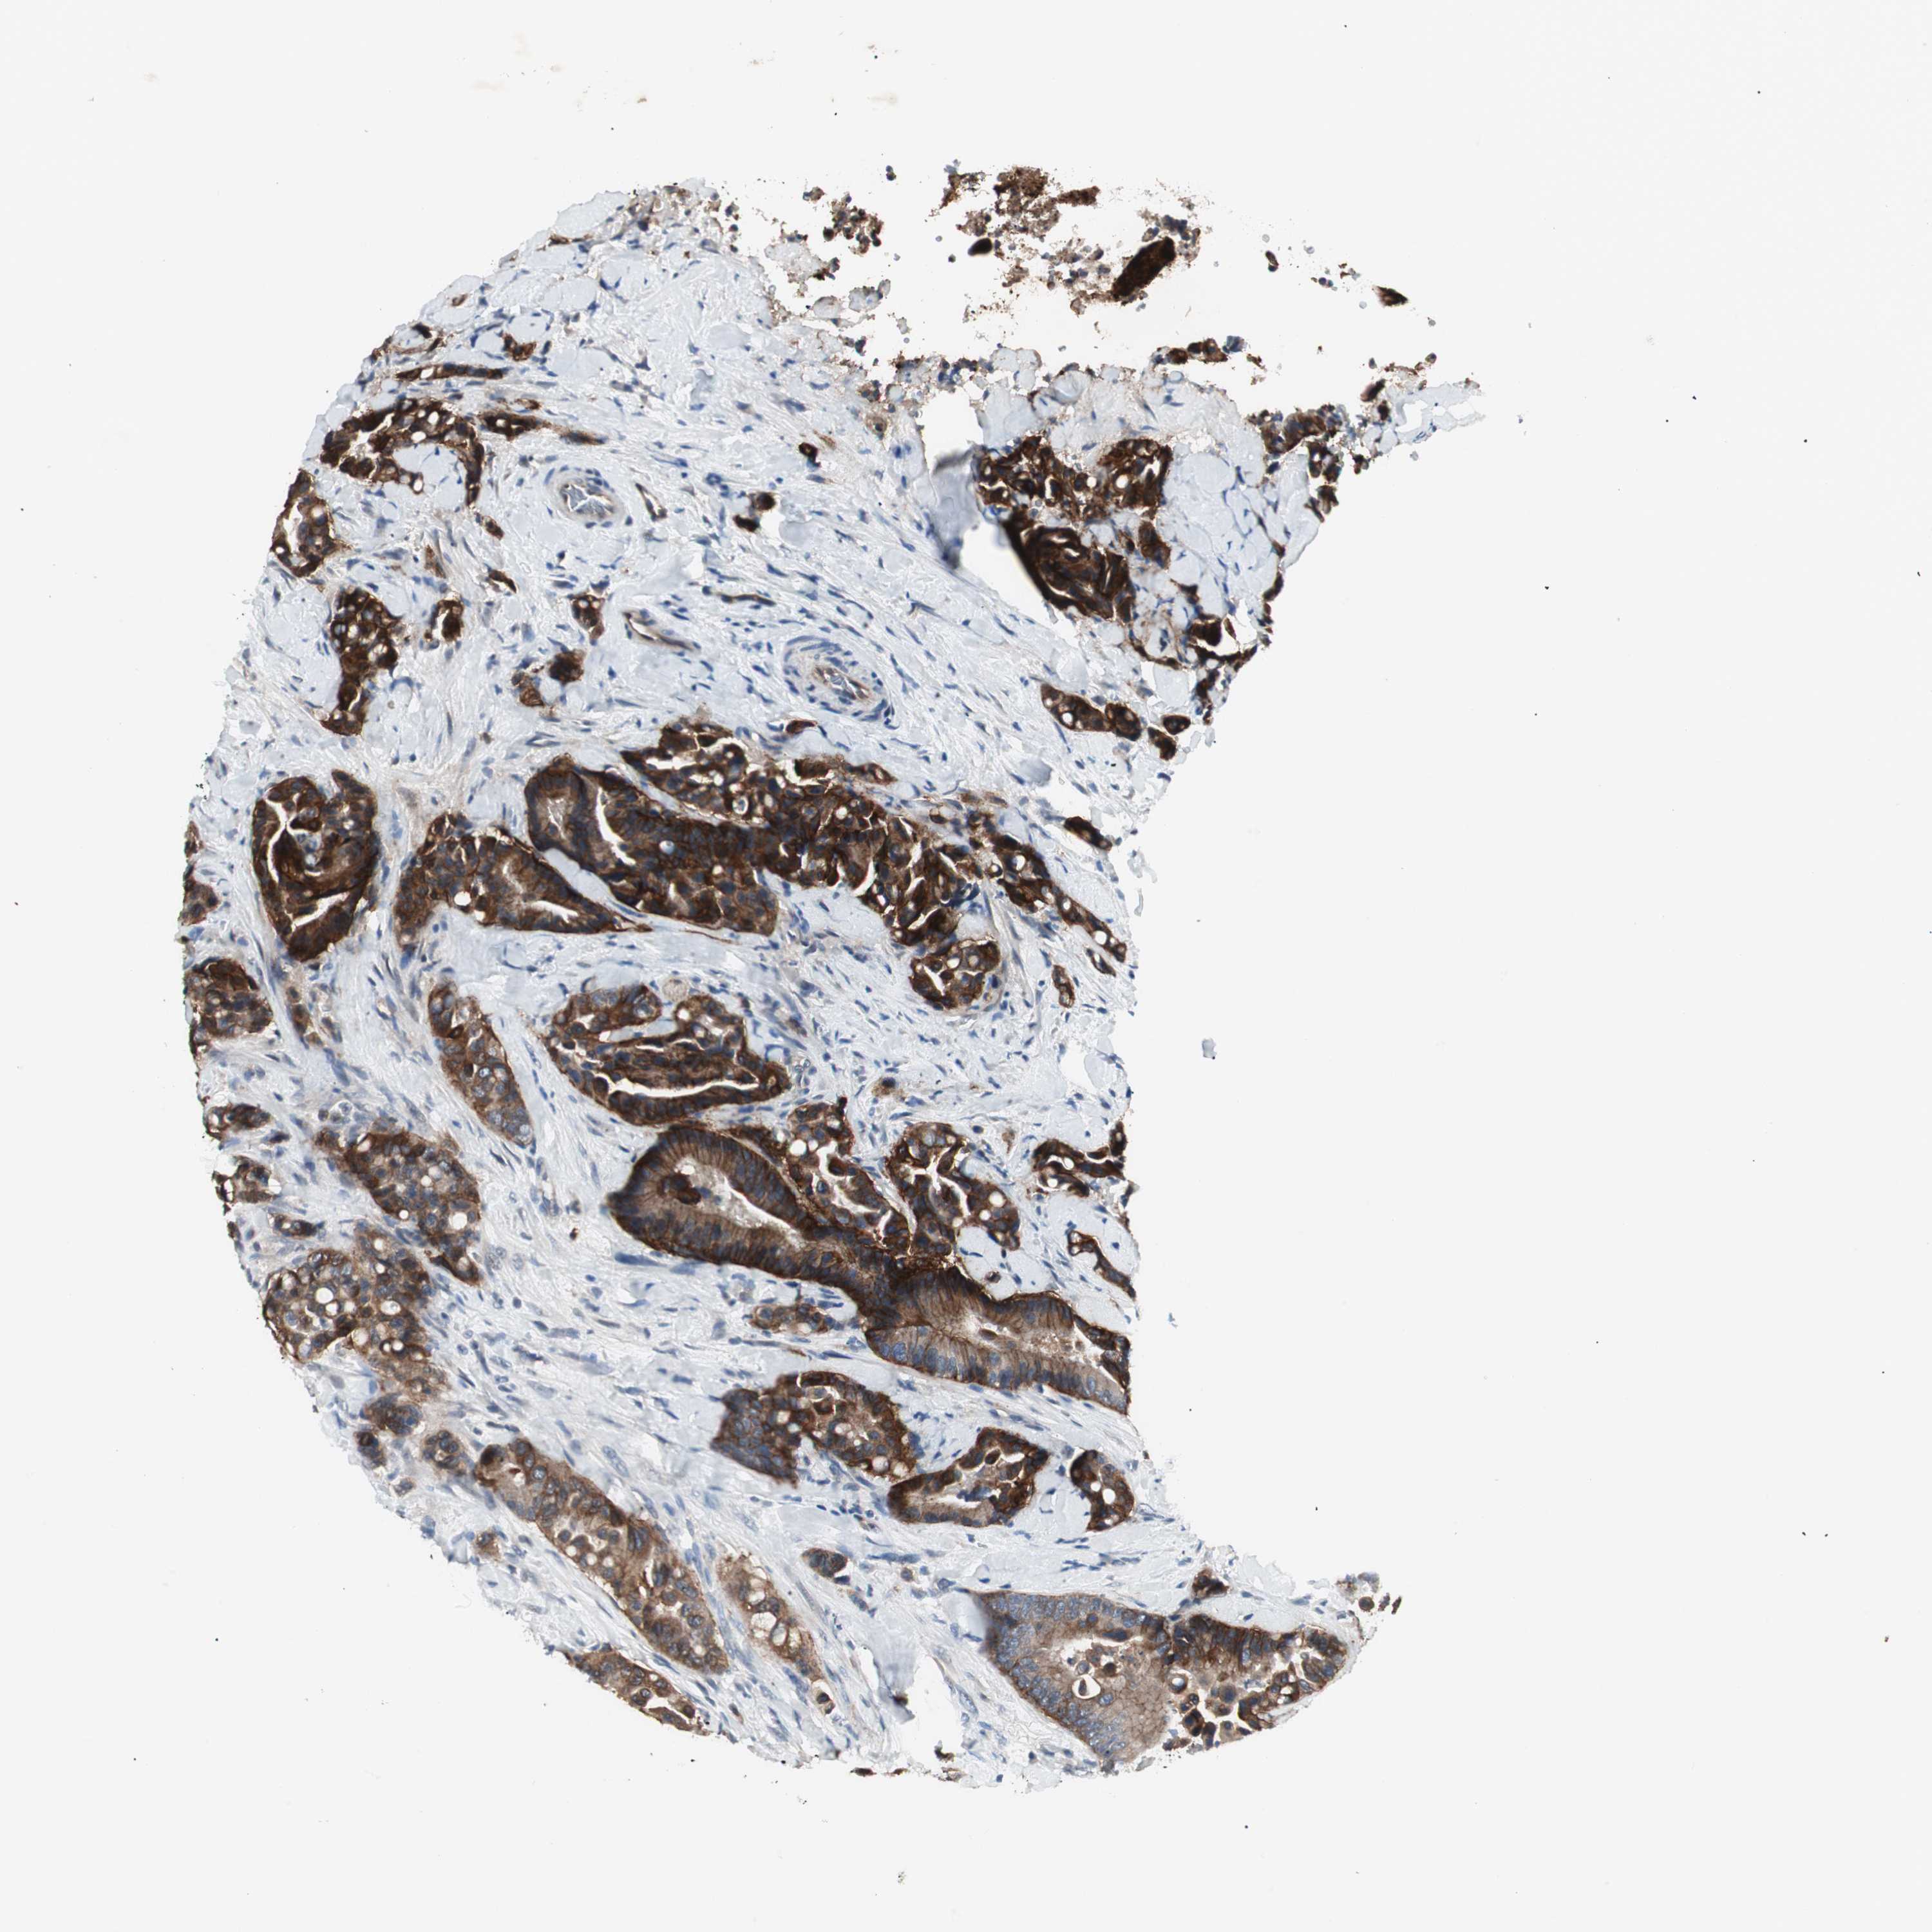

CANCER COLORECTAL CANCER Show tissue menu

Colorectal cancer

Colon adenocarcinoma